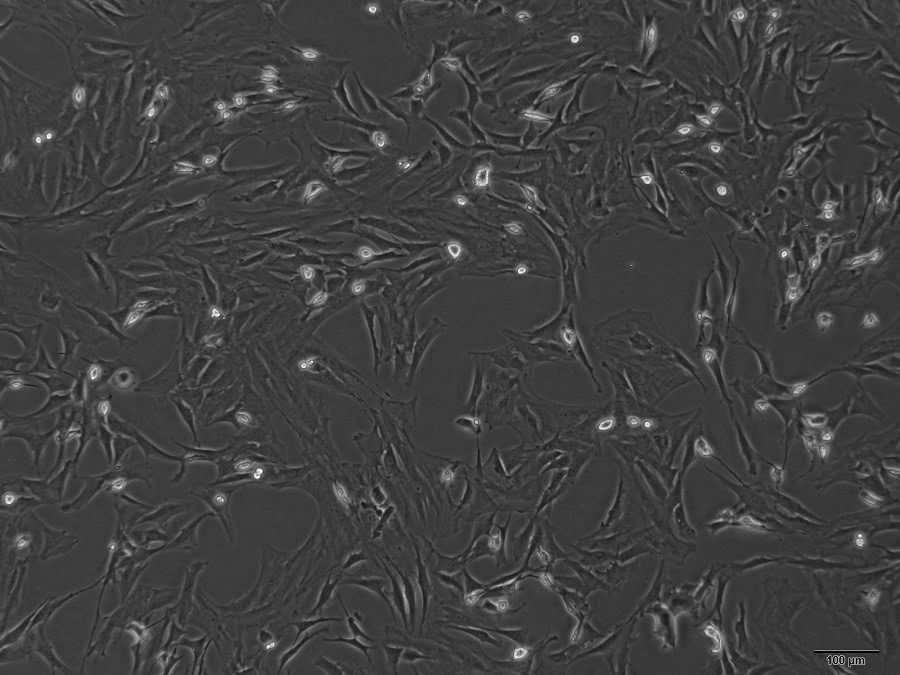

鼠源骨髓間充質(zhì)干細(xì)胞

1、產(chǎn)品名稱:小鼠骨髓間充質(zhì)干細(xì)胞MouseBone marrow mesenchymal stem cells,BM-MSCs

2、組織來源:正常小鼠骨髓

3、產(chǎn)品規(guī)格:25cm2培養(yǎng)瓶

小鼠骨髓基質(zhì)系統(tǒng)存在的骨髓間充質(zhì)干細(xì)胞(Bonemarrow mesenchymal stem cells,BM-MSCs)是一種除造血干細(xì)胞以外的、具有多向分化潛能的干細(xì)胞,可以向骨、軟骨、

肌組 織、皮膚、脂肪、神經(jīng)等多種組織分化,因此可以作為組織工程中的種子細(xì)胞。

本公司生產(chǎn)的小鼠骨髓間充質(zhì)干細(xì)胞(BM-MSCs)采用沖洗骨髓的方法制備而來,細(xì)胞總量約為5X105個(gè)/瓶,細(xì)胞純度可達(dá)90%以上,且不含有HIV-1、 HBV、HCV、支原體、細(xì)菌

酵母和真菌等。